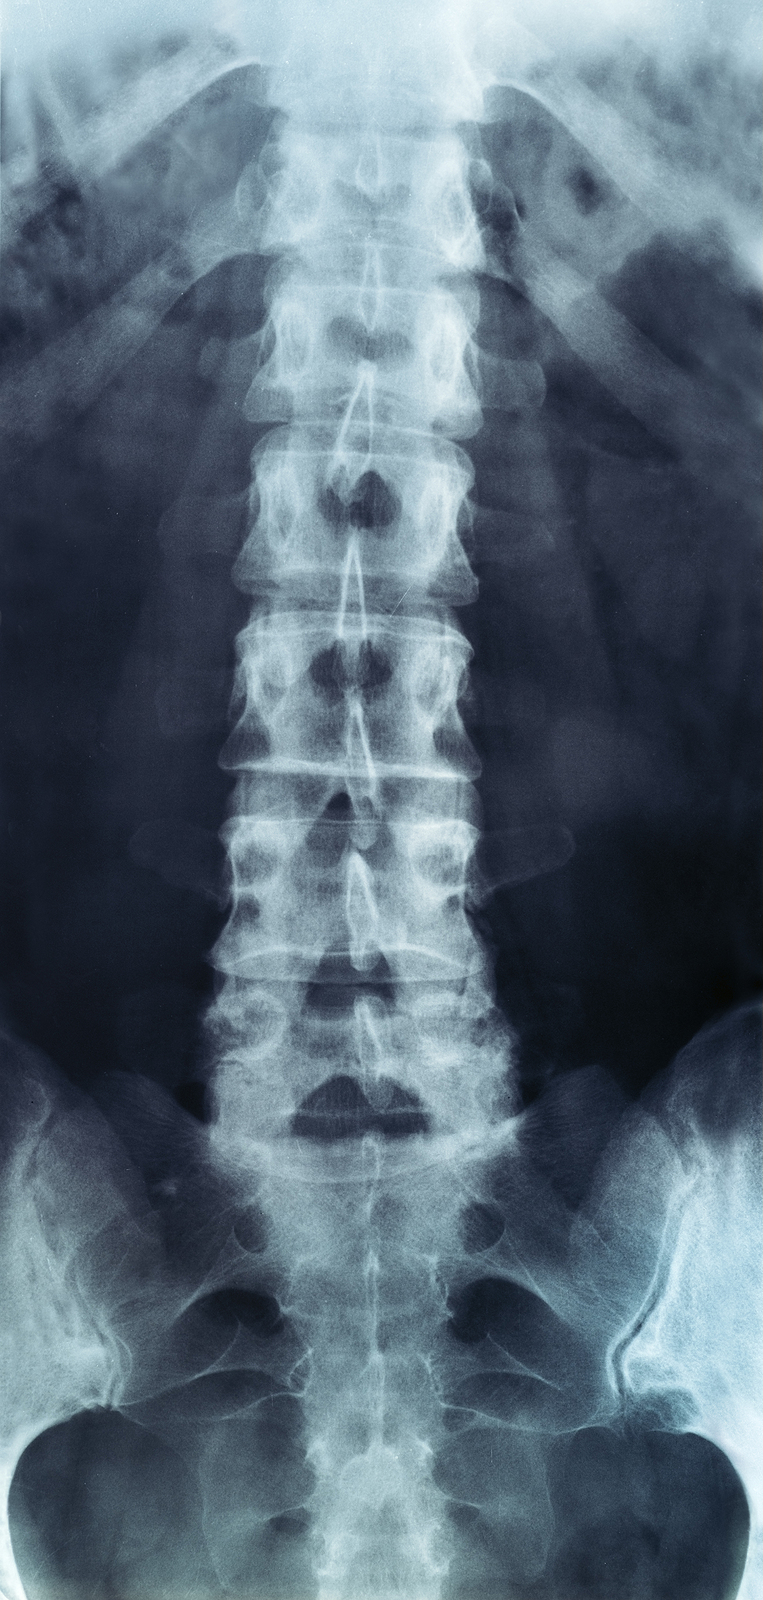

The human spine is made up of 24 spinal bones, called vertebrae, as well as the sacrum and the coccyx. The sacrum is a triangular bone near the bottom of the spine and the coccyx is more commonly known as the tailbone.

Vertebrae are stacked on top of one another to create the spinal column. The spinal column gives the body its form and helps sustain an upright position.

The lumbar spine—where pain is often experienced—is made up of five vertebrae positioned near the bottom of the spinal column. Doctors often refer to these vertebrae as levels L1, L2, L3, L4 and L5. The ‘L’ refers to ‘lumbar’. The lowest vertebra, L5, is connected to the top of the sacrum—a triangular bone at the base of the spine that is located between the two pelvic bones. Some people are born with an extra or sixth lumbar vertebra called L6. Having an extra vertebra doesn't usually cause physical problems.

Most people with low back pain will NOT need x-rays or other tests to diagnose and treat their pain. In some cases, if an x-ray or other diagnostic could be helpful, your physical therapist will refer you to a doctor for further diagnostic imaging.

When acute back pain occurs, diagnostic tests are not routine, as diagnostic tests that are completed unnecessarily may produce misleading findings. In numerous interesting studies, patients have demonstrated major structural changes in different back or spinal structures on x-rays in the absence of physical symptoms.

If diagnostic tests are deemed necessary, there are several different tests that your doctor may recommend. Radiological imaging tests allow your doctor to see the anatomy of your spine, which assists the determination of what may be causing your back pain. Knowing what structures may be contributing to your back pain may help further direct the most appropriate treatment to assist you.

X-rays

X-rays are usually the first test ordered before any of the more specialized tests are completed. X-rays use electromagnetic radiation to show problems with bones and can also reveal problems such as fractures, infections, or bone tumors. X-rays of the spine can give your doctor information about bone alignment and can demonstrate how much degeneration has occurred in the spine. Both alignment and degeneration can affect the amount of space in the neural foramina and between the discs, which subsequently impacts the nerves in the area. This is important information your health care professional can use to establish a treatment plan.